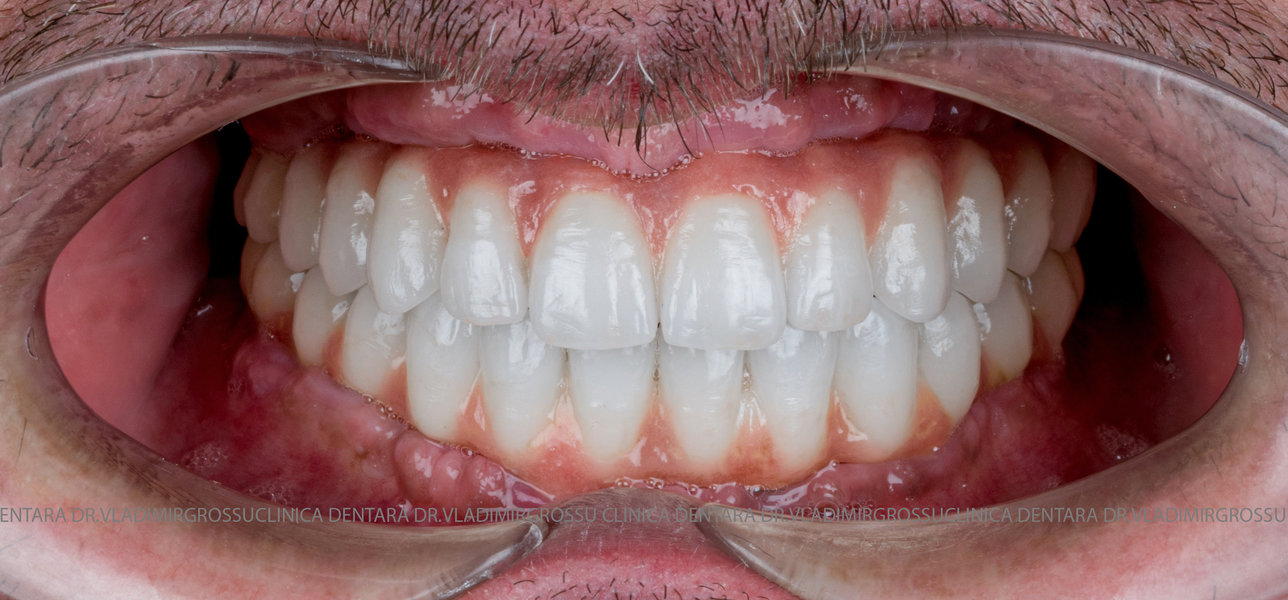

Cazuri clinice conceptul All-on-6